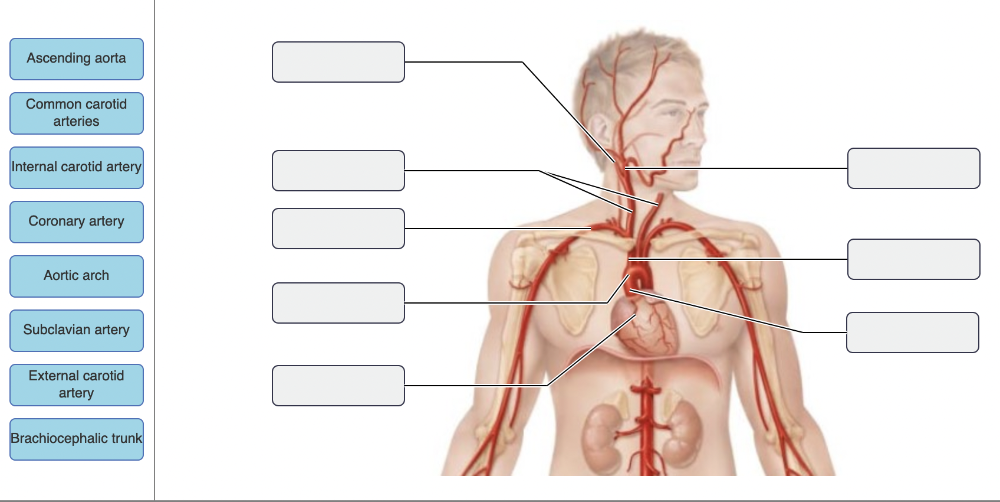

A thrombus (blood clot) in the first branch of the arch of the aorta would affect the flow of blood to the ________.

- left upper arm

- left side of the head and neck

- right side of the head and neck and right upper arm

- myocardium of the heart

right side of the head and neck and right upper arm

From what artery does the right common carotid artery arise?

- brachiocephalic trunk

- aortic arch

- external carotid artery

- internal carotid artery

brachiocephalic trunk

Ex.

The brachiocephalic trunk is found only on the right side of the body, and it splits to form the right common carotid artery and the right subclavian artery. These two arteries arise independently from the aorta on the left side of the body.